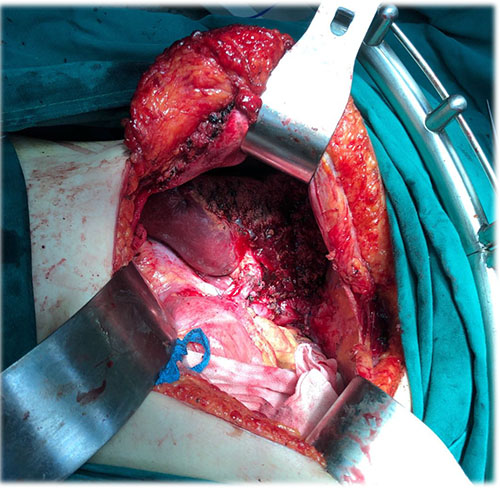

左肝肝癌---扩大左半肝切除+尾状叶切除